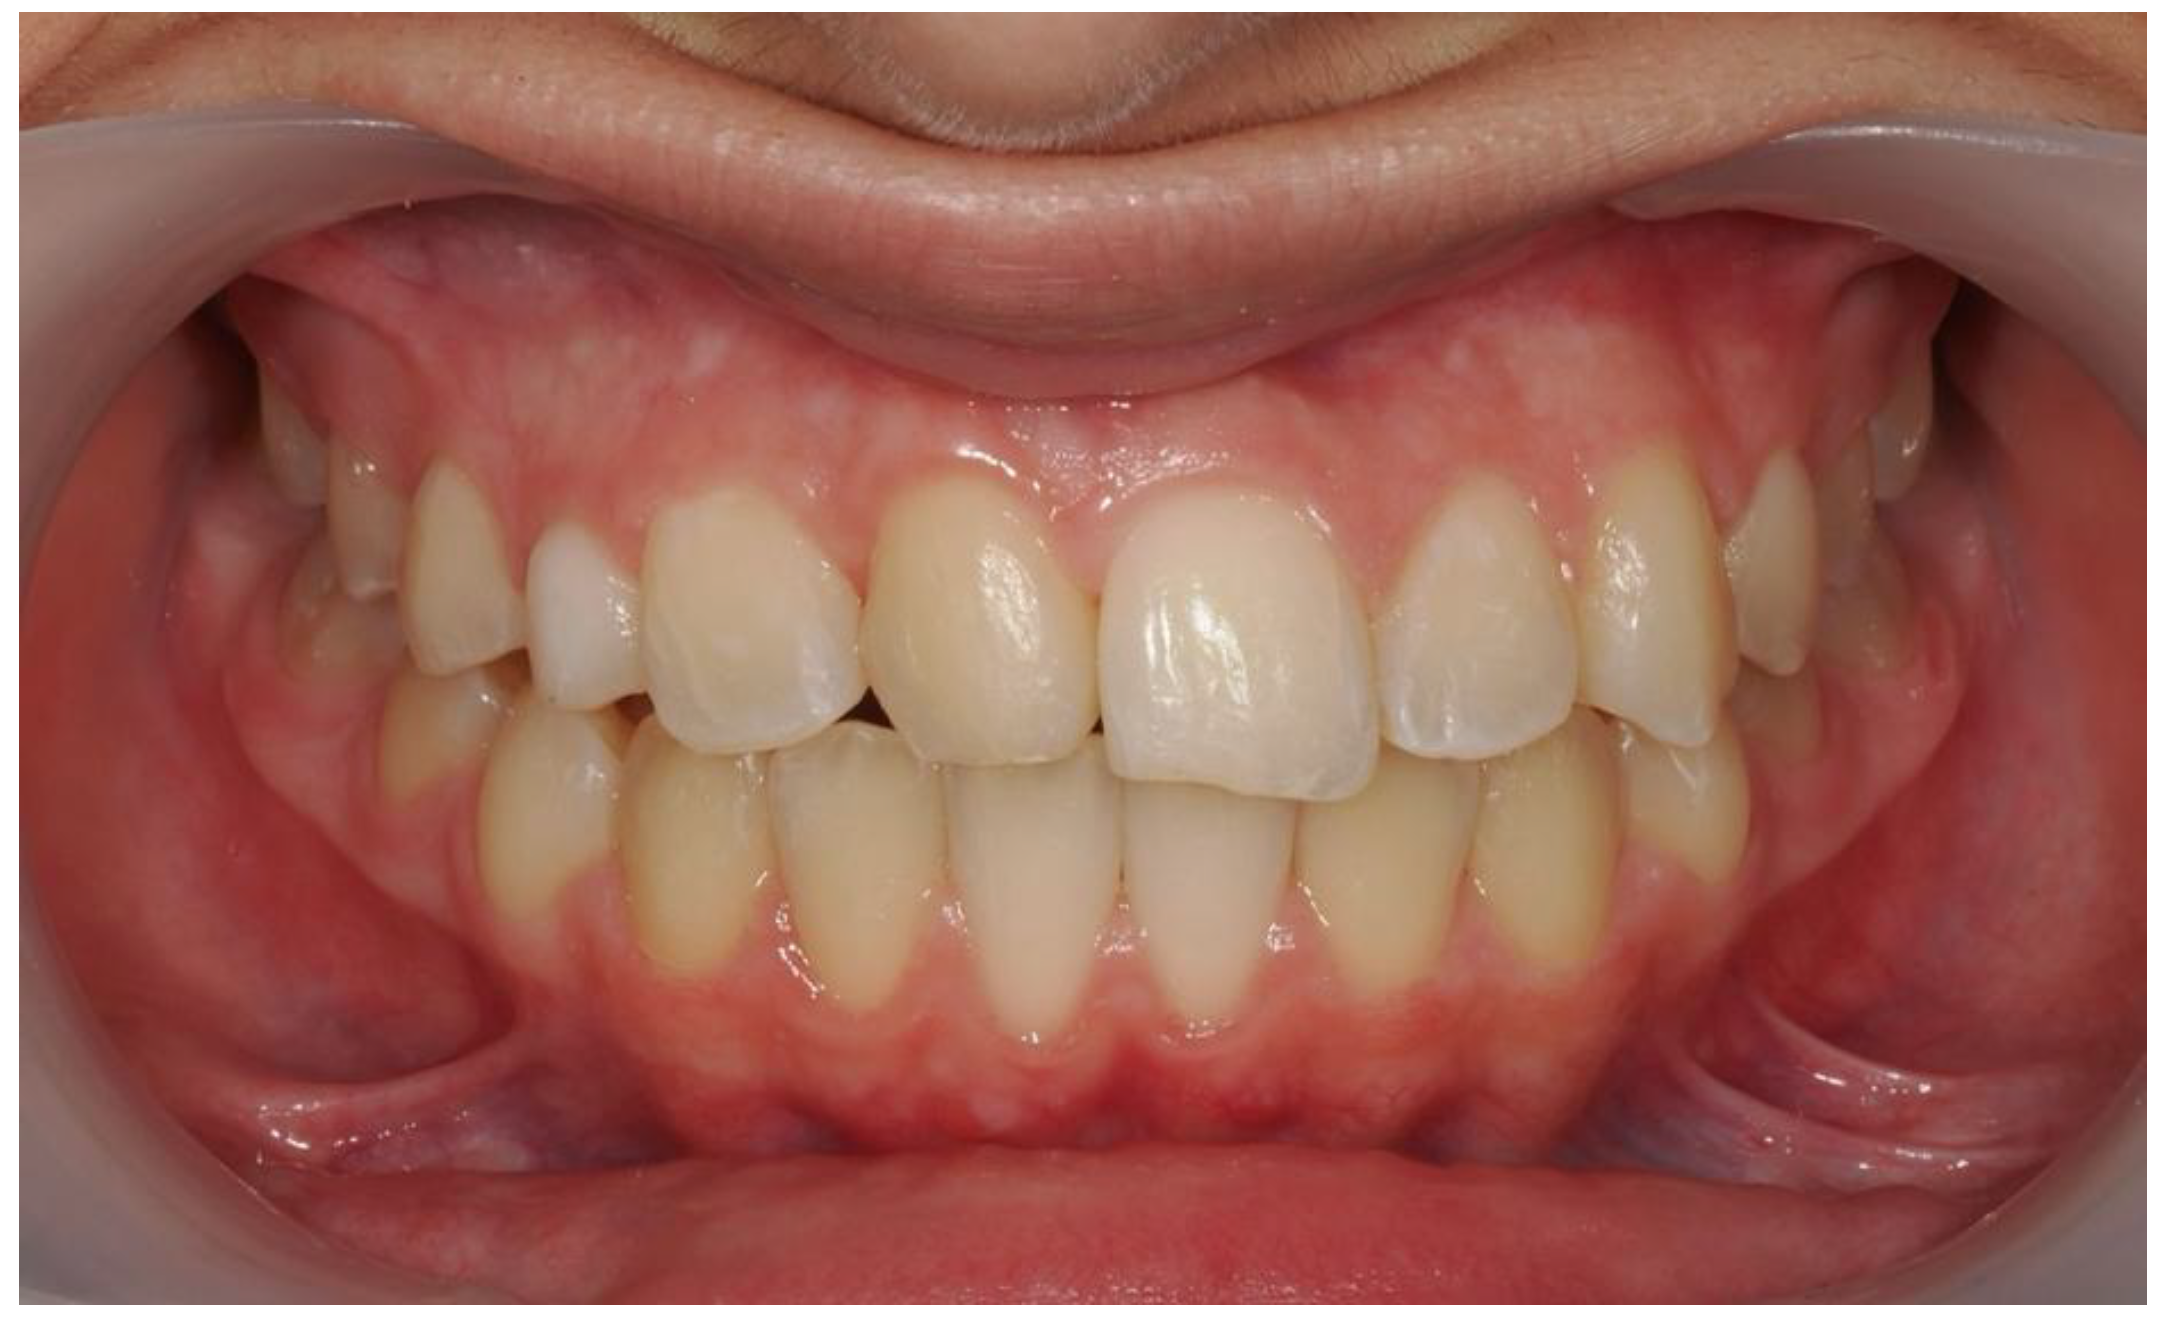

| Pinho T., Amaral R. 2025 | ♀ 13 YO | Mx.C.I1 | C | R | V (impacted) | Cl I | Maintained | -Total root resorption of tooth #11 due to the position of the ectopic canine |

3.2. Clinical Case